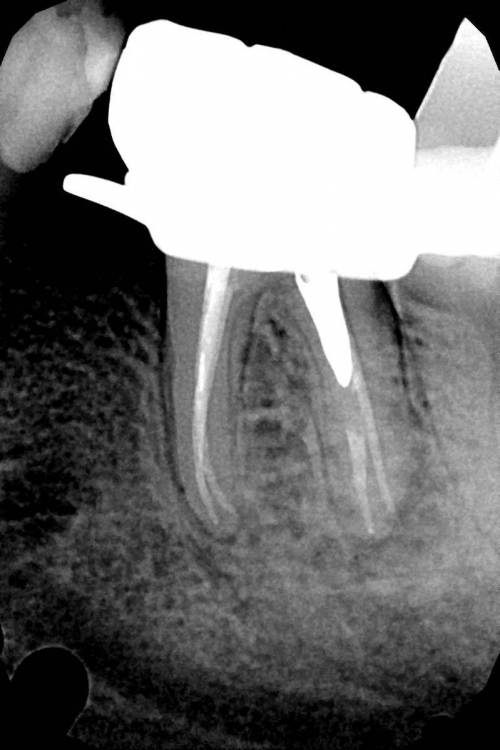

Ico Опубликовано 5 апреля, 2022 Автор Поделиться Опубликовано 5 апреля, 2022 Обострение хронического периодонтита зуб 36. После первичного эндо пропущен ДБ канал,зуб был восстановлен циркониевой вкв + циркон коронка.На пропИл до устья ушло 5 боров.Мед мех стандартный 40к+F1,паковка гибрид с Эйчем.2 визита по 2 и 1.5 часа. 3 1 Ссылка на комментарий